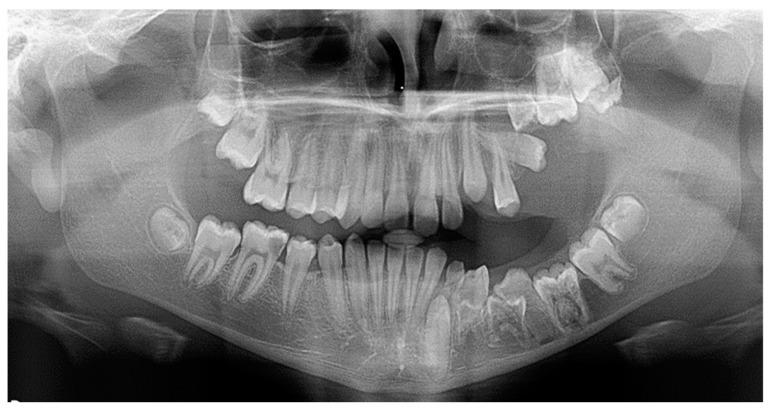

Panoramic radiographs of 1400 patients that sought orthodontic treatment in private practice were retrieved and examined. All teeth that had not been erupted at the time of the examination while their root formation was completed were considered impacted.

In total, 212 out of 1400 patients had at least one impacted tooth (15.14%). The highest incidence of tooth impaction was in the canines of the maxilla, followed by the central incisors of the maxilla, the second molars of the mandible and the second premolars of the mandible. The most common etiological factors responsible for the impaction were the ectopic eruption pathway, loss of space in the arch, the ankylosis of the deciduous teeth and the presence of supernumerary teeth.

方法

在1400名患者中,共有212名患者至少有一颗阻生牙(15.14%)。牙齿阻生的最高发生率在上颌尖牙,其次是上颌中切牙、下颌第二磨牙和下颌第二前磨牙。导致阻生的最常见病因是异位萌出道、牙弓间隙丧失、乳牙粘连和多生牙的存在。